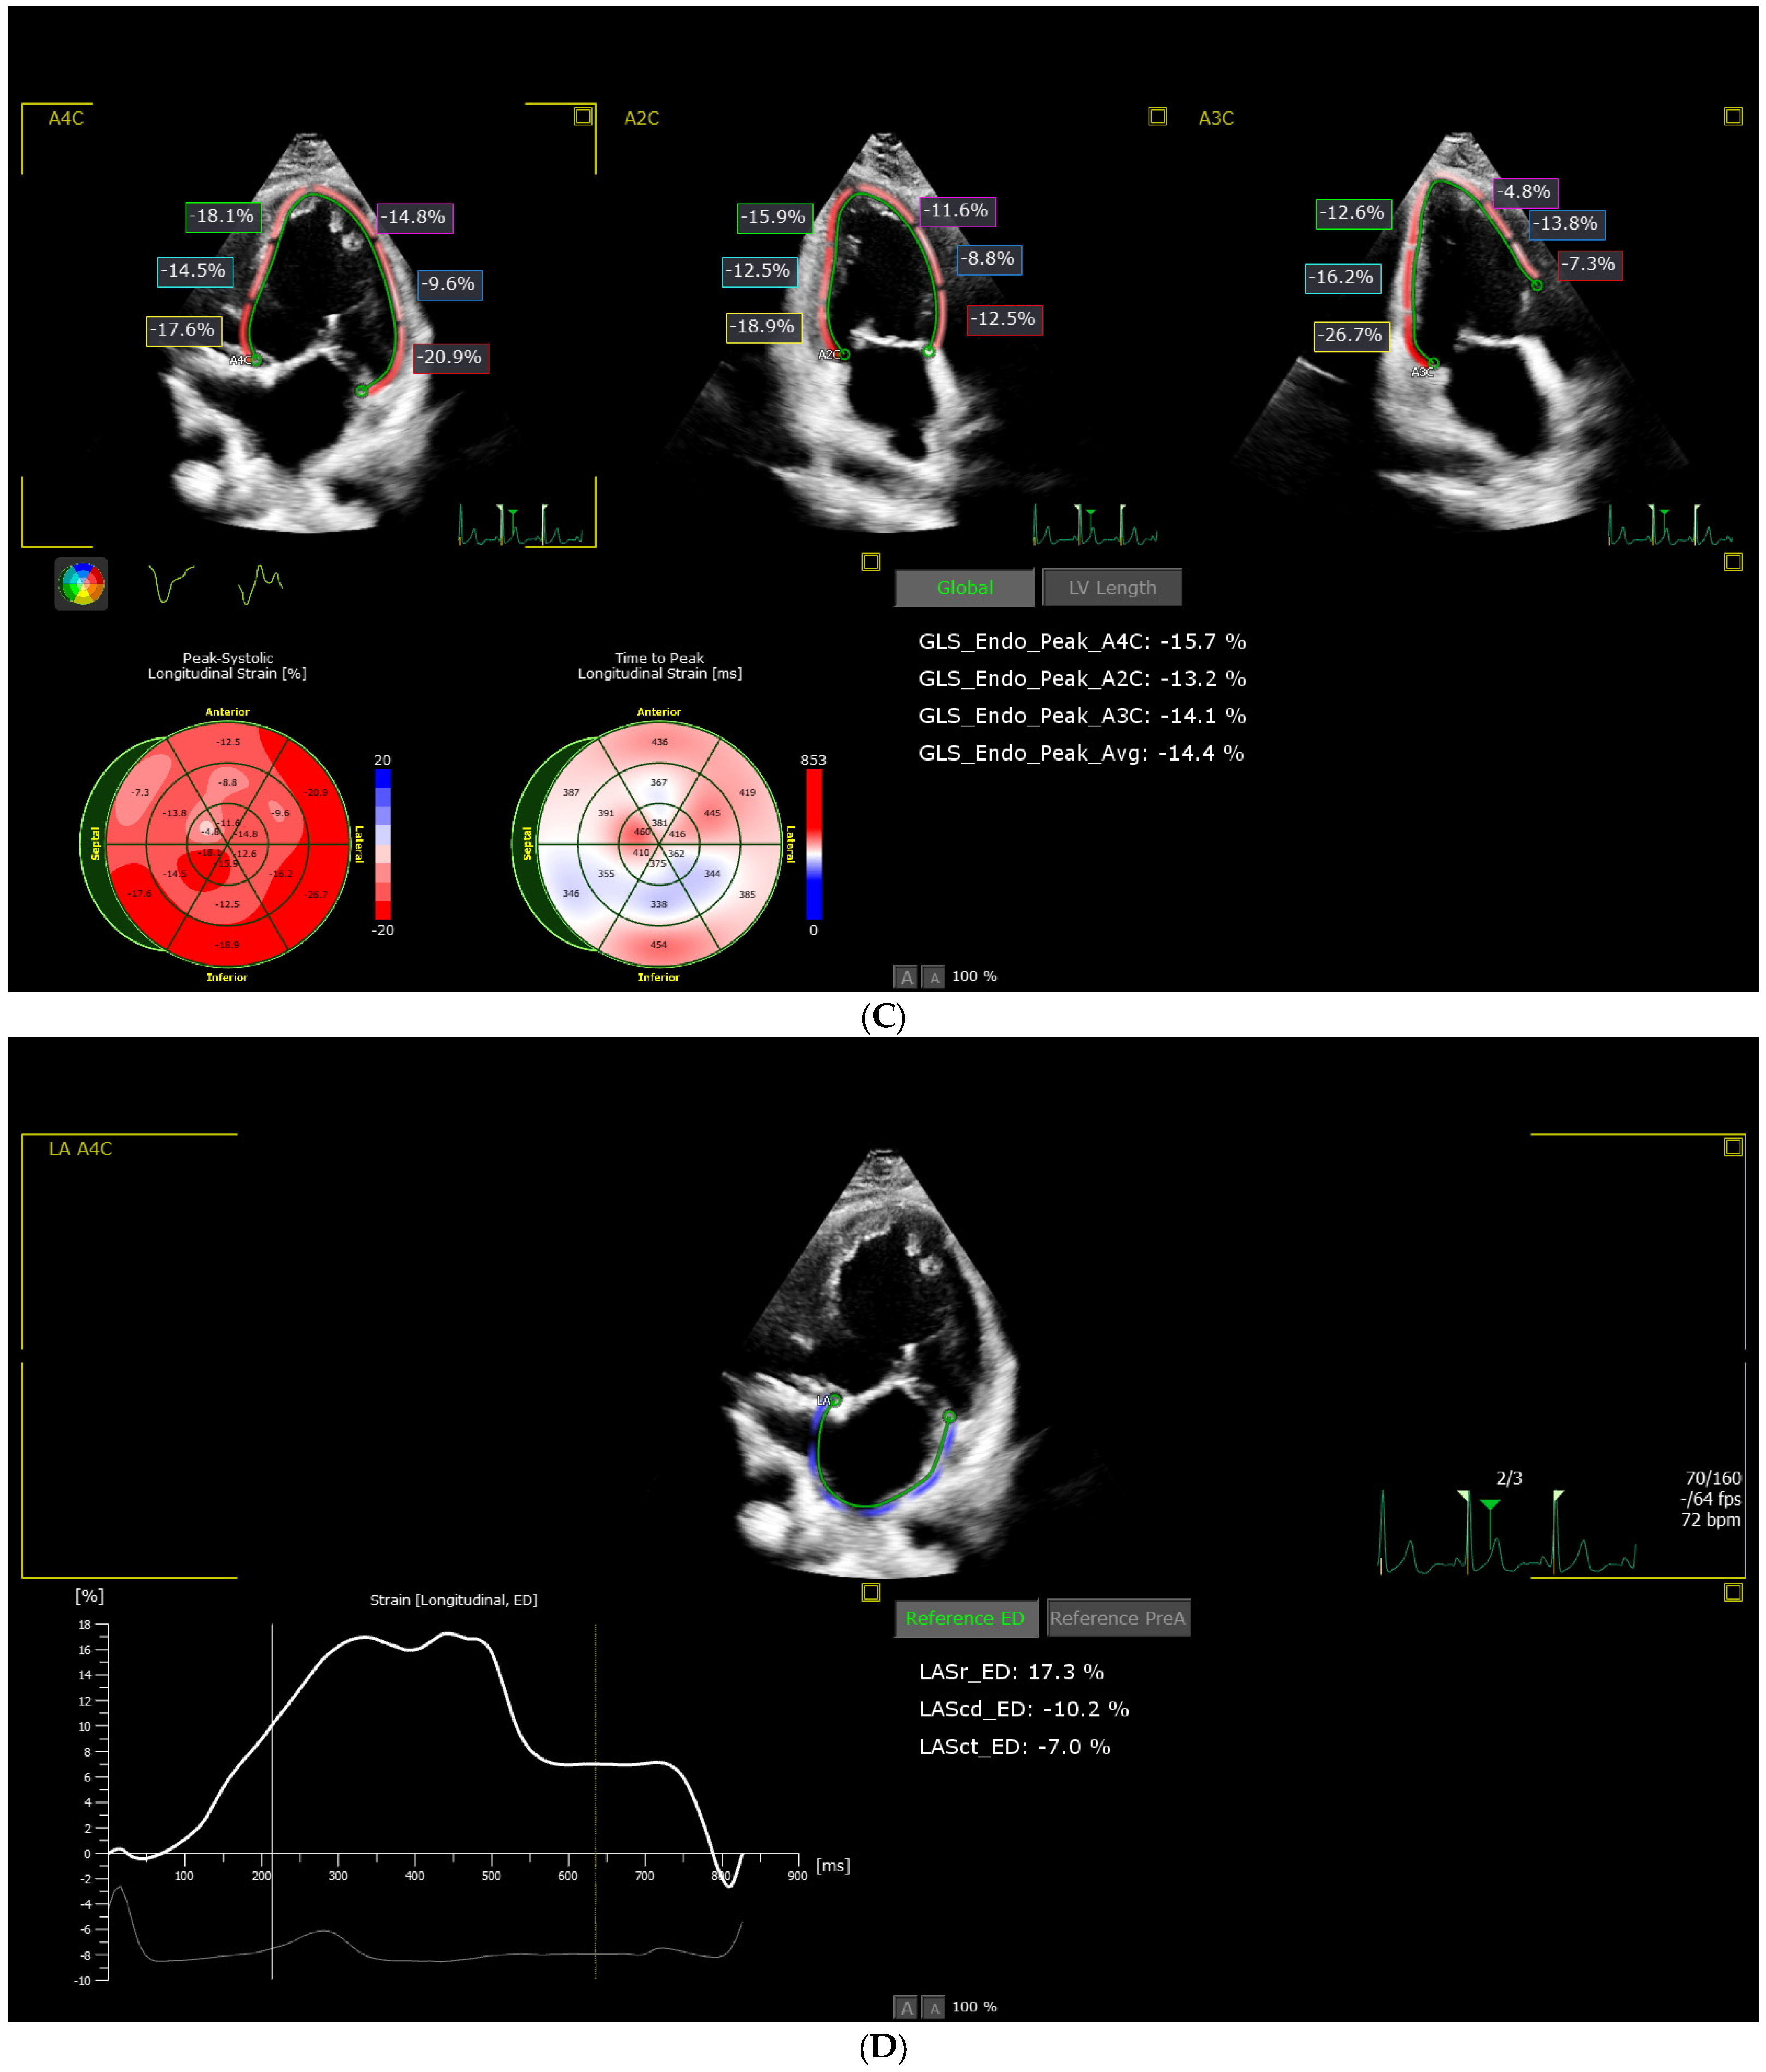

2.2.3. Speckle Tracking Acquisition and Analysis

3.4. Comparison of Two-Dimensional Echocardiographic Segmental and Global Left Ventricle Longitudinal Strain Indices in Controls and Fontan Patients

| LV_GLS | −22.36 (1.42) | −13.80 (2.48) | <0.0001 * (b) | <0.0001 * |